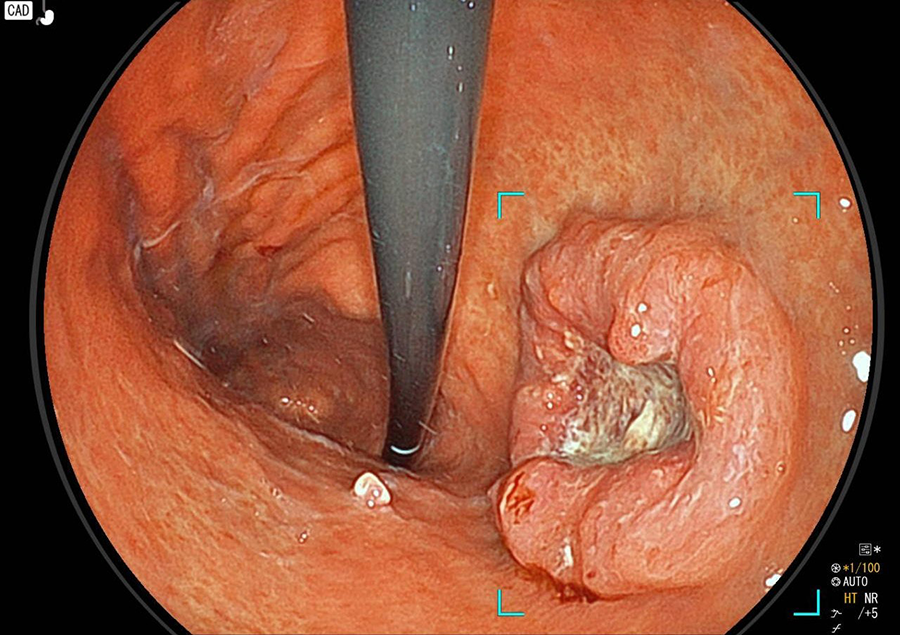

胃カメラ検査では、口又は鼻から内視鏡を挿入し、食道・胃・十二指腸の一部を観察します。直接胃や食道の粘膜を観察することができるので、色調や微妙な凹凸の変化が分かり、潰瘍・炎症・ポリープ・腫瘍などの診断が可能です。

胃カメラでわかる病気/病変

検査の様子